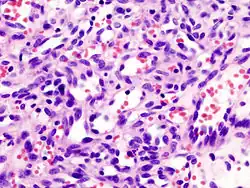

Mikro: Proliferation der Intima und fibrinoide Nekrose

Makro: Hauptsächlich die kleinen bis mittelgroßen Arterien sind betroffen. Es kommt zur Ausbildung perlschnurartig angeordneter kleiner Knötchen

D.: Muskelbiopsie